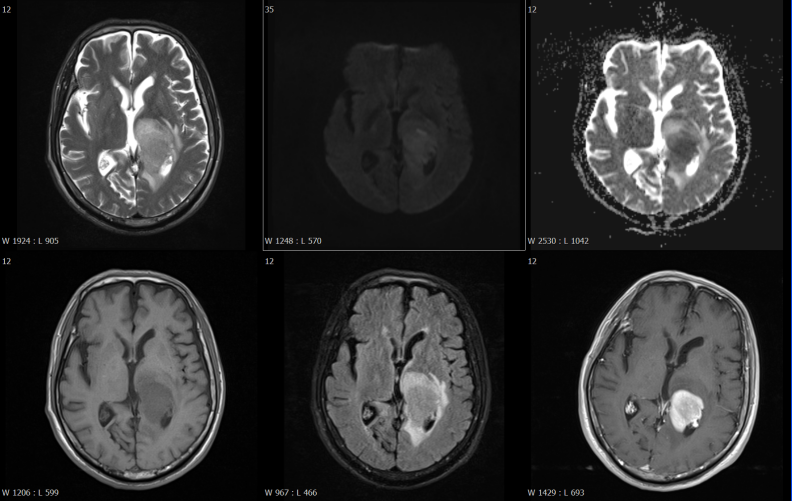

磁共振檢查方面,開展了高技術(shù)的增強(qiáng)掃描動態(tài)分析,動態(tài)灌注掃描、波譜分析,為腫瘤鑒別提供了有效方法,比如腦內(nèi)膠質(zhì)瘤、淋巴瘤的鑒別。

富血供病變---高級別膠質(zhì)瘤